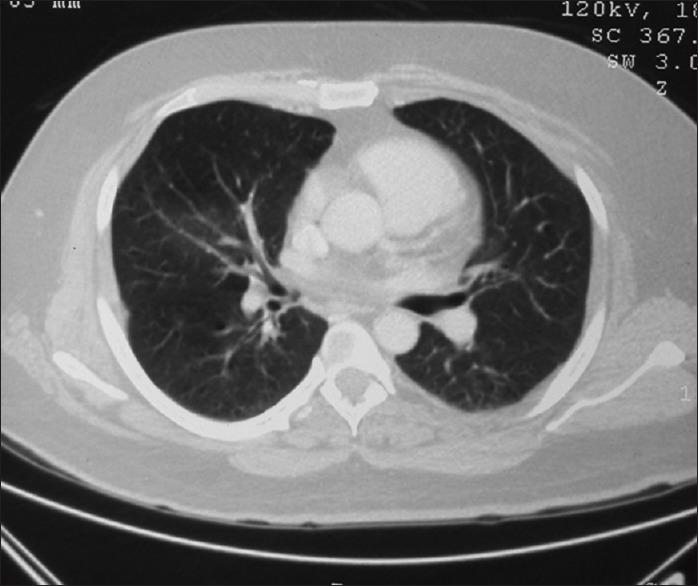

We report a case of hypothyroidism, obstructive sleep apnea (OSA) with persistent daytime hypoxemia. Cause of hypoxemia was two arteriovenous (AV) malformations in the lower lobe of the lung. We must be alert to other causes of hypoxemia in patients of OSA with persistent daytime hypoxemia.

我们报告一例甲状腺功能减退症合并阻塞性睡眠呼吸暂停(OSA)且伴有持续性日间低氧血症的病例。低氧血症的原因是肺下叶的两个动静脉畸形。对于患有持续性日间低氧血症的OSA患者,我们必须警惕低氧血症的其他原因。